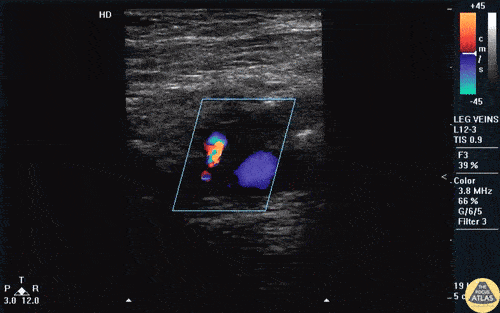

Vascular - AV Fistula

A male presented with thigh pain and swelling with a history of an untreated stab wound 2 months prior. A sagittal view over the femoral artery revealed bidirectional flow indicative of an AV fistula. Image courtesy of Robert Jones DO, FACEP @RJonesSonoEM Director, Emergency Ultrasound; MetroHealth Medical Center; Professor, Case Western Reserve Medical School, Cleveland, OH View his original post here